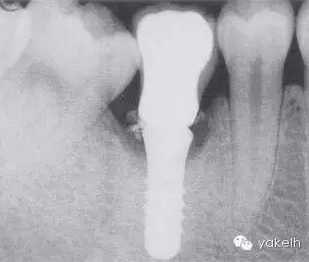

LR6由2顆種植體修復(fù)。2顆種植體之間距離過近(圖.1)。通常情況下,單個(gè)磨牙缺失僅需植入單個(gè)直徑較寬的種植體即可。影像學(xué)顯示這2顆種植體周圍有大量的骨喪失(種植體周圍炎表現(xiàn))(圖2)。

圖2 影像學(xué)顯示2顆種植體相合并,彼此之間距離過近,已經(jīng)喪失了25%~50%的支持骨組織。